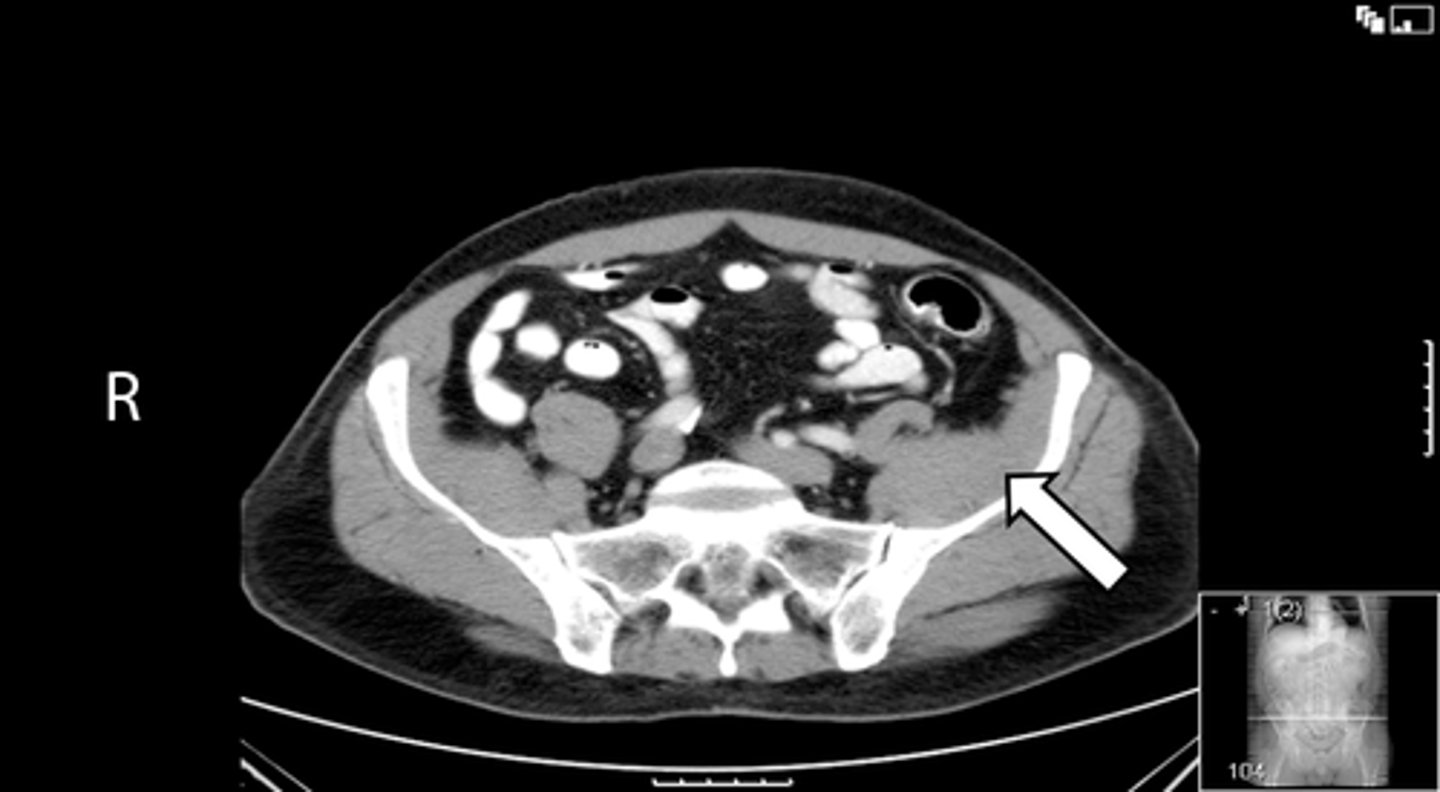

Axial bony pelvis CT

What is the image?

38

L acetabulum

<p>What is indicated in the image?</p>

New cards

What is indicated in the image?

40

L piriformis muscle

42

R piriformis muscle

44

Sacrum